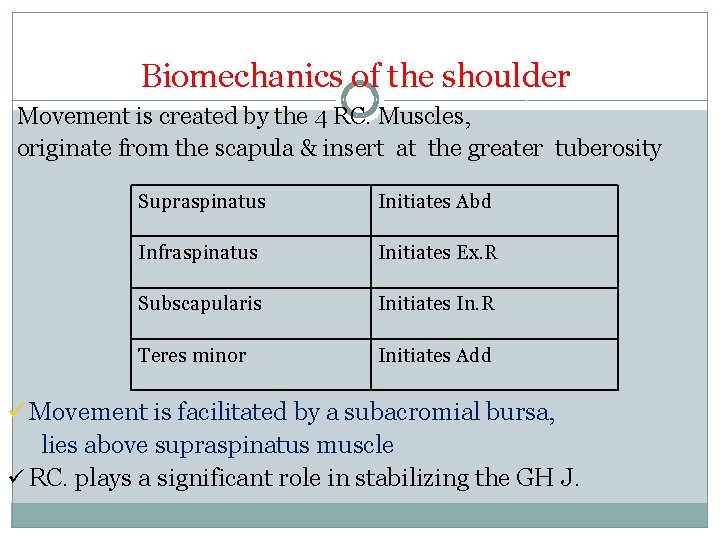

ANATOMY AND FUNCTION Rotator cuff It is composed of four muscular units: Supraspinatus Infraspinatus Teres minor Subscapularis

Biomechanics of the shoulder Movement is created by the 4 RC. Muscles, originate from the scapula & insert at the greater tuberosity Supraspinatus Initiates Abd Infraspinatus Initiates Ex. R Subscapularis Initiates In. R Teres minor Initiates Add ü Movement is facilitated by a subacromial bursa, lies above supraspinatus muscle ü RC. plays a significant role in stabilizing the GH J.